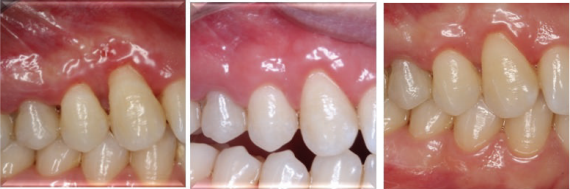

患者1月、6月、12月后复诊,恢复良好,无复发。 牙龈纤维瘤在临床属于较常见疾病,多采用手术切除方式,注意要与其他类型牙龈增生相鉴别。手术切除纤维瘤后,若缺损较大,尤其实在美学区,影响美观,可以利用周围皮瓣进行修复。术后菌斑控制也很重要。